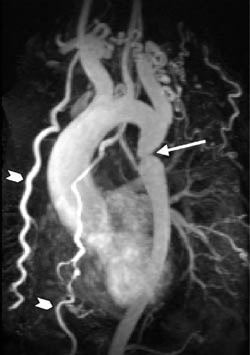

Medfødt hjertesykdom

Ikke-invasiv bildediagnostisk utredning av medfødt hjertesykdom er i første rekke en oppgave for ekkokardiografi med doppler. Bruken av MR er derfor langt på vei bestemt av hvor langt man kommer med den undersøkelsen. MR er særlig godt egnet til å avklare komplisert anatomi (3, 4) og kan også bedre enn ekkokardiografi brukes til å vurdere både høyre og venstre ventrikkels funksjon (7). MR kan benyttes ved postoperativ kontroll av flere tilstander (3, 5), ikke minst hos barn og unge. Ved en forholdsvis enkel tilstand som coarctatio aortae (fig 1) vil MR alene som regel gi tilstrekkelig informasjon både pre- og postoperativt (3).